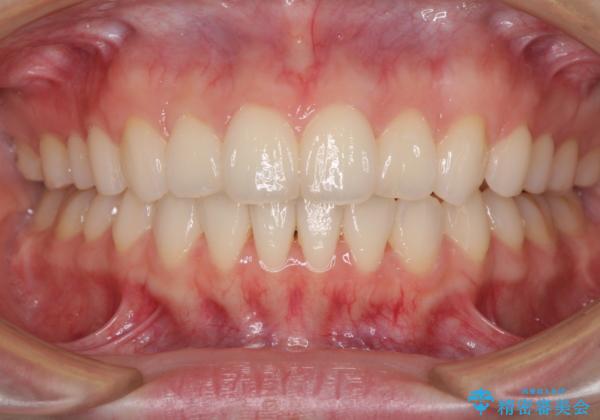

毎日しっかりと装着してくださったので、概ねシミュレーション通りに歯を移動させることができました。

治療前には接触することのなかった上下の前歯が接触するようになり、食事の際前歯でものをかみ切れるようになりました。

気にしていた口元の印象が改善され、患者様には大変満足していただきました。